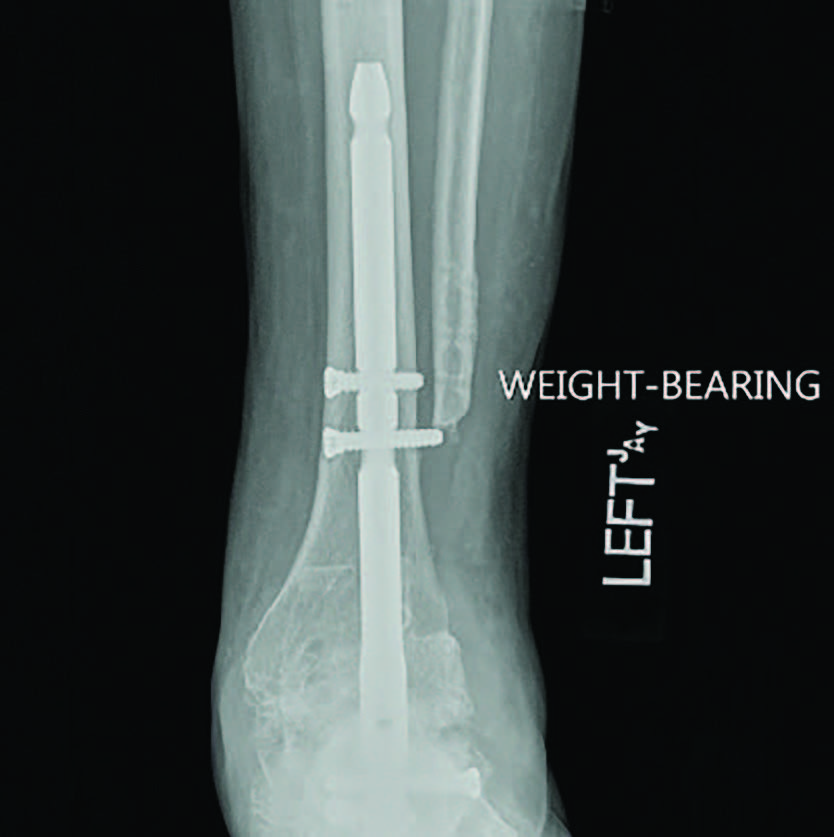

For this patient, I ultimately performed a subtalar joint fusion with distal tibial autograft. She subsequently went on to develop a symptomatic non-union at six months postoperatively and collapse of her talus (see third image above). She again had medical optimization and we planned for a femoral head allograft reconstruction with Augment bone graft and intramedullary nail fixation. The patient went on to clinical success and there was demonstrated healing on a CT scan at four months post-op. She is now weightbearing in a shoe at two years post-op (see fourth and fifth images above).